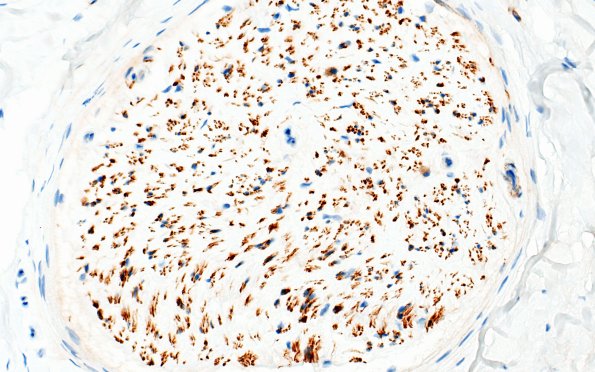

Washington University Experience | PERIPHERAL NEUROPATHY | 4 AXONAL DEGENERATION | 1 H&E & IHC | 14D End Stage Nerve (Case 14) CD56 40X 2

There are Schwann cells residual in the endoneurium which are CD56 immunoreactive and are thought to represent denervated Bands of Büngner and/or non-myelinating Schwann cells in normal adults. (CD56 IHC)